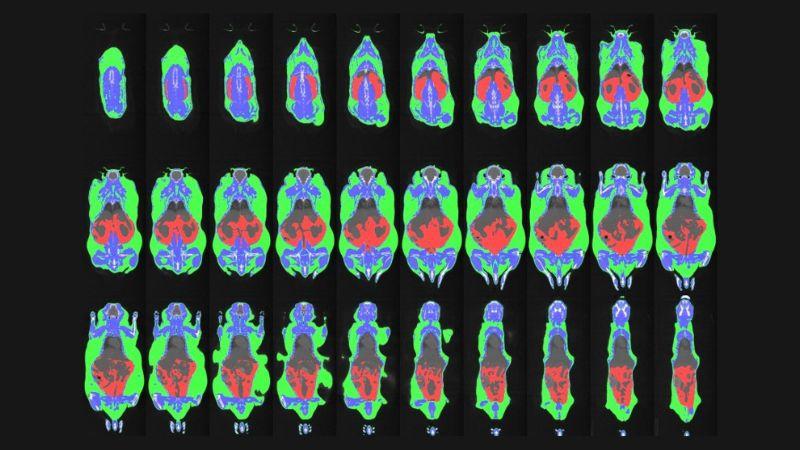

PCP DSI Telemetry EEG/EMG-Deep Brain EEG | PCI uCT-in vivo Imaging |

PCP DSI Telemetry EEG/EMG-Seizures | PCI uCT-ex vivo Imaging (Trabecular and Cortical Bone Quantification) |

PCP DSI Telemetry EEG/EMG-Sleep | PCI 2D Digital X-ray Skeletal Imaging |

PCP Electrocardiogram, Anesthetized | PCI Dual-Emission X-ray Absorptiometry |